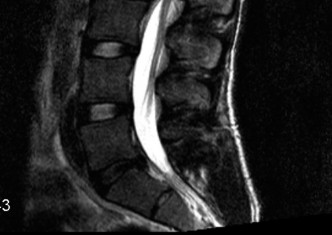

To evaluate the neural elements and the soft tissue structures, a comprehensive MRI of the lumbar spine without contrast was obtained. The T2-weighted sagittal and axial sequences confirmed the Grade 2 anterolisthesis and demonstrated severe bilateral foraminal stenosis at L5-S1. The exiting L5 nerve roots were severely compressed between the hypertrophied, fibrocartilaginous pseudarthrosis tissue of the pars defect dorsally, and the bulging, degenerated L5-S1 disc and superior endplate of S1 ventrally. Furthermore, the MRI revealed Modic Type II changes (fatty replacement of the subchondral bone marrow) in the adjacent vertebral endplates, confirming chronic biomechanical stress and discogenic degeneration. The central canal remained relatively patent, which is characteristic of isthmic spondylolisthesis, as the posterior neural arch is left behind during the anterior translation of the vertebral body.

Five years later, the patient, now a 20-year-old collegiate athlete, presented back to our clinic with a drastically altered clinical picture. He was now experiencing severe, unrelenting, and constant pain in his lower back that severely limited his mobility. Crucially, the pain character had evolved; he now reported sharp, shooting, electric-like pain radiating from his lower back, deep into his left posterior buttock, and extending down the lateral aspect of his left thigh and calf. This transition from purely axial mechanical pain to a profound radicular symptom complex indicates that the underlying pathology had progressed from a localized bony defect to a structural instability causing direct neural compression. The progressive anterior slip of L5 on S1 had led to dynamic foraminal stenosis, trapping the exiting L5 nerve root against the fibrocartilaginous mass of the pars nonunion and the superior endplate of S1.